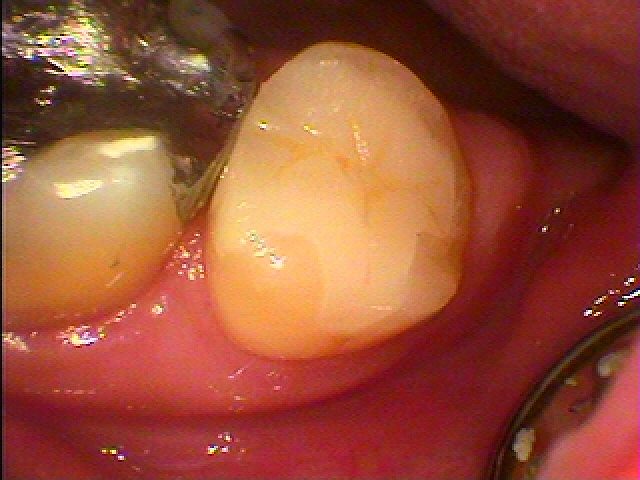

セレックセラミックにて修復しています